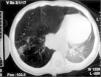

Lactante de raza árabe de 5 meses y 20 días de edad con cuadro de 3 meses de evolución caracterizado por tos persistente, dificultad respiratoria creciente, fiebre intermitente no termometrada y estancamiento ponderal desde el tercer mes de vida. Fue derivada para intervención al Servicio de Cirugía Infantil de nuestro hospital con el diagnóstico de enfisema lobar congénito. Sus padres eran tosedores crónicos, sin diagnóstico etiológico. Su peso era de 5kg (< percentil 3). Se mantuvo apirética y con saturaciones de O2 > 97 % desde su ingreso. En la exploración física existía un aumento del diámetro anteroposterior del tórax, con tiraje, taquipnea con 60 resp./min, hipoventilación marcada en hemitórax derecho y desviación del latido cardíaco hacia la izquierda. La radiografía anteroposterior de tórax mostraba desplazamiento mediastínico hacia la izquierda, hiperinsuflación del lóbulo medio e inferior derechos, atelectasia en el lóbulo superior derecho y pérdida de volumen en el pulmón izquierdo. Ante las dudas planteadas sobre el diagnóstico inicial, decidimos ampliar los estudios. En el hemograma existía leucocitosis de 21.920/μl a expensas de mononucleares, velocidad de sedimentación globular de 26mm, con bioquímica, inmunoglobulinas, subpoblaciones linfocitarias y gasometría sin alteraciones. El estudio para el virus de la inmunodeficiencia humana resultó negativo. En la tomografía computarizada (TC) torácica (fig. 1) se apreciaba hiperinsuflación del lóbulo medio con herniación hacia el mediastino anterior y marcas vasculares evidentes, lo que iba en contra del diagnóstico inicial. En cortes superiores se evidenciaba un conglomerado adenopático paravertebral derecho, con calcificaciones e imágenes radiológicas sugestivas de infiltrado pulmonar subpleural en resolución. Ante la sospecha de lesión intrabronquial causante de un enfisema obstructivo, se llevó a cabo fibrobroncoscopia, que reveló en el bronquio intermediario un granuloma endobronquial que ocluía completamente la luz del mismo y compresión extrínseca peribronquial (fig. 2). En las muestras de lavado broncoalveolar y aspirado gástrico, la tinción de Ziehl-Neelsen fue negativa y los cultivos en medio de Lowenstein-Jensen mostraron el crecimiento de micobacterias. La prueba de tuberculina fue de 1mm. Entre los contactos próximos a la paciente, la madre tuvo una reacción tuberculínica de 33mm, infiltrado pulmonar en lóbulos superiores y una lesión cavernosa en la radiografía de tórax. Se instauró tratamiento con isoniacida, rifampicina y piracinamida durante los dos primeros meses, y prednisona durante un mes, continuando con los dos primeros fármacos los 4 meses siguientes. Al mes de evolución se objetivó una marcada mejoría clinicorradiológica.

TC torácica. Hiperinsuflación del lóbulo medio con herniación hacia el mediastino anterior con marcas vasculares evidentes. Se aprecian adenopatías paravertebrales derechas, con calcificaciones en su interior e imágenes radiológicas sugestivas de infiltrado pulmonar subpleural en resolución.